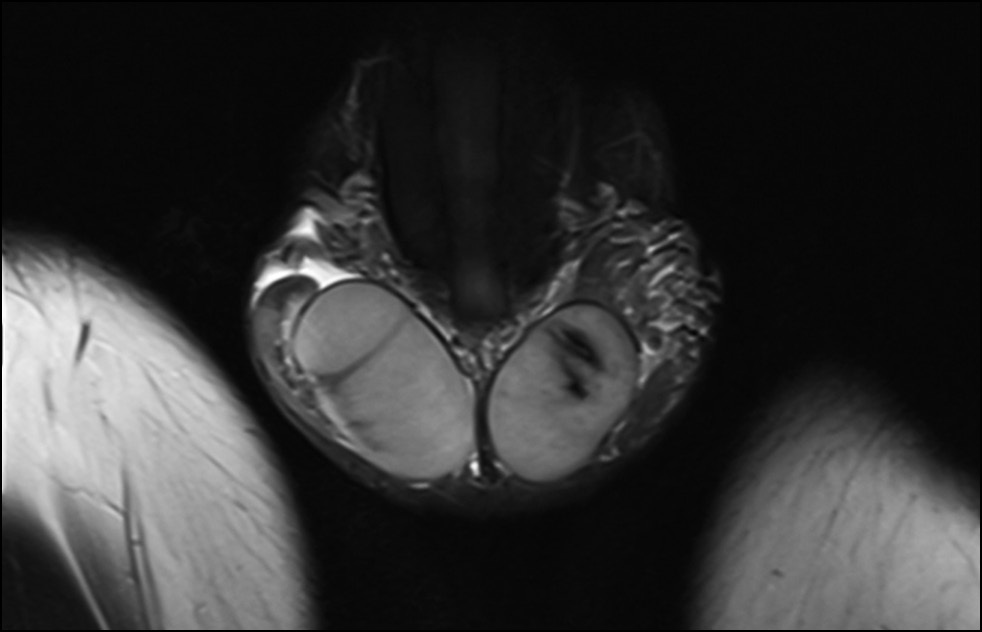

В рассматриваемом случае МРТ подтвердила нормальное расположение и морфологическую структуру правого яичка. При этом левое яичко и его придаток отличались меньшими размерами по сравнению с правым. В его структуре в области верхнего полюса был обнаружен неоднородный участок, состоящий из нескольких линейных очагов сосудистых нарушений (рис. 3–5) [6].

Рис. 3. В области верхнего полюса левого яичка (T2-взвешенное изображение) обнаружен очаг неоднородной структуры, состоящий из ряда линейных полостей, свидетельствующих о наличии ишемии.

Рис. 4. Область ишемии левого яичка на аксиальном срезе (T2-взвешенное изображение).